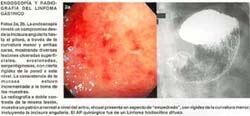

Se consignan fotos representativas del Linfoma Gástrico en composiciones de la Foto 1 a la Foto 7.

Nosotros hemos presentado de acuerdo a los informes de nuestro Servicio de Gastroenterología, una descripción desde el punto de vista endoscópico que sigue claramente las pautas de la escuela japonesa para referirnos específicamente al Cáncer Gástrico Temprano con todas sus variedades (46), y de otro lado, también nos hemos guiado para describir al Cáncer Gástrico Avanzado siguiendo la clasificación de Borrmann, y se ha destacado el Cáncer Gástrico no Clasificable como tipo V, según la misma escuela (85), finalmente; hemos podido identificar en un grupo importante de pacientes, prácticamente desde el inicio, formas endoscópicas que nos sugerían firmemente la presencia del Linfoma Gástrico (35, 92). También hemos rescatado que compartimos una terminología semejante dentro de la descripción endoscópica de las Neoplasias Gástricas con países vecinos como Chile (57). La literatura occidental publicada en la década de los 50, revelaba que, la forma macroscópica del Linfoma Gástrico descrita por A.W. Allen (5), si bien precisa que suele ser con frecuencia no distinguible del Carcinoma Gástrico, logra puntualizar los siguientes tipos: lesión ulcerada de bordes prominentes e infiltrantes, lesión tumoral o de crecimiento anular, lesión esencialmente infiltrativa tipo linitis plástica, y en un 25% de los casos, el Linfomaparecía ser multicéntrico en su origen, pues el estómago podía contener varias lesiones tumorales ulceradas aisladas. Este patrón se ha repetido con mayor o menor cercanía según consignan otros autores (20, 33, 58, 60, 93). Sin embargo, publicaciones posteriores también empezaron a reconocer que al lado de las lesiones macroscópicamente descritas, coincidían formas de presentación mas bien de diseminación superficial (66), e inclusive en el INEN, ya se reconocía desde la década del 70, que el patrón endoscópico más frecuentemente encontrado consistía en: lesiones ulceradas tipo volcán, el engrosamiento de los pliegues y las lesiones francamente tumorales, además de un patrón de gastritis con punteado hemorrágico (73). Cuando se evalúa exclusivamente pacientes con Maltoma Gástrico, con estadio clínico I, los hallazgos endoscópicos han sido clasificados como: úlceras, lesiones tumorales, erosiones, cambios atípicos de mucosa y lesiones no visibles (59), otros reportes de pacientes con características similares, revelan hallazgos endoscópicos de úlceras gástricas, gastritis y mucosa congestiva (77). En series de oriente y sobre 233 especímenes resecados de Linfoma Gástrico entre 1962-1994, el tipo macroscópico utilizado de acuerdo a la clasificación de Watanabe mostró: 100 pacientes con la forma de masa tumoral, 96 pacientes con la forma de diseminación superficial, 23 pacientes no clasificables y 14 pacientes con la forma infiltrante-difusa (66). Recientemente en el año 2002, G. Tytgat ha sintetizado y propuesto 4 formas de presentación: (1) lesiones polipoideas, protuberantes y exofíticas, (2) compromiso predominantemente infiltrativo y poco distendible, (3) lesiones irregulares, ulceradas multifocales, (4) cambios inflamatorios con eritema irregular. (96)

Tenemos la impresión de que, sea cual fuere la clasificación endoscópica utilizada para describir el Linfoma Gástrico (89), creemos que se puede precisar o definir un patrón endoscópico característico que está dado por la presencia de lesiones ulceradas gástricas múltiples de aspecto geográfico, bordes anfractuosos, algunas estrelladas, otras crateriformes, y que tienden a localizarse mayormente entre el cuerpo y el antro, habiéndonos permitido hacer el diagnóstico del Linfoma Gástrico prácticamente desde el inicio del manejo del paciente, lo que concuerda a su vez tanto con la serie descrita por P. Llorens en la Universidad de Chile (57), como con otras series occidentales (35), si bien es cierto que, hay reportes que revelan que en el Linfoma Gástrico no hay un patrón endoscópico específico (31, 32, 88, 93), hay autores que al contrario, manifiestan de manera categórica y con lo que ciertamente coincidimos, de que las lesiones ulceradas tipo volcanes o crateriformes, no están descritas en otras lesiones malignas del estómago que no sea el Linfoma Gástrico y ellos consideran que las lesiones ulceradas tipo cráteres de volcán o crateriformes, o úlceras grandes estrelladas, son características del Linfoma Gástrico (35), o son lesiones virtualmente 100% específicas para el Linfoma, además refieren que en más de la mitad de los pacientes ellos pueden sospechar Linfoma cuando en el hallazgo endoscópico encuentran estas lesiones ulceradas múltiples crateriformes (92). La serie nuestra encuentra un patrón endoscópico de Linfoma en el 21% de los casos, que coincide con el 21% de otros autores (92), por otra parte, la serie de la Universidad de Chile encuentra un patrón endoscópico de Linfoma en el 55% de sus pacientes (57), y dentro del mismo contexto, en nuestro instituto se encuentra que más del 75% de los pacientes que acuden con diagnóstico de Linfoma Gástrico tienen un aspecto mascroscópico de cáncer avanzado tipo Borrmann, y a la inversa, hay series occidentales, donde encuentran que el 77% de sus pacientes, son Linfomas malignos de bajo grado (91), todo lo cual muestra realidades diferentes dentro del manejo de estas neoplasias, ciertamente, las formas superficiales y de bajo grado serán las más indolentes.